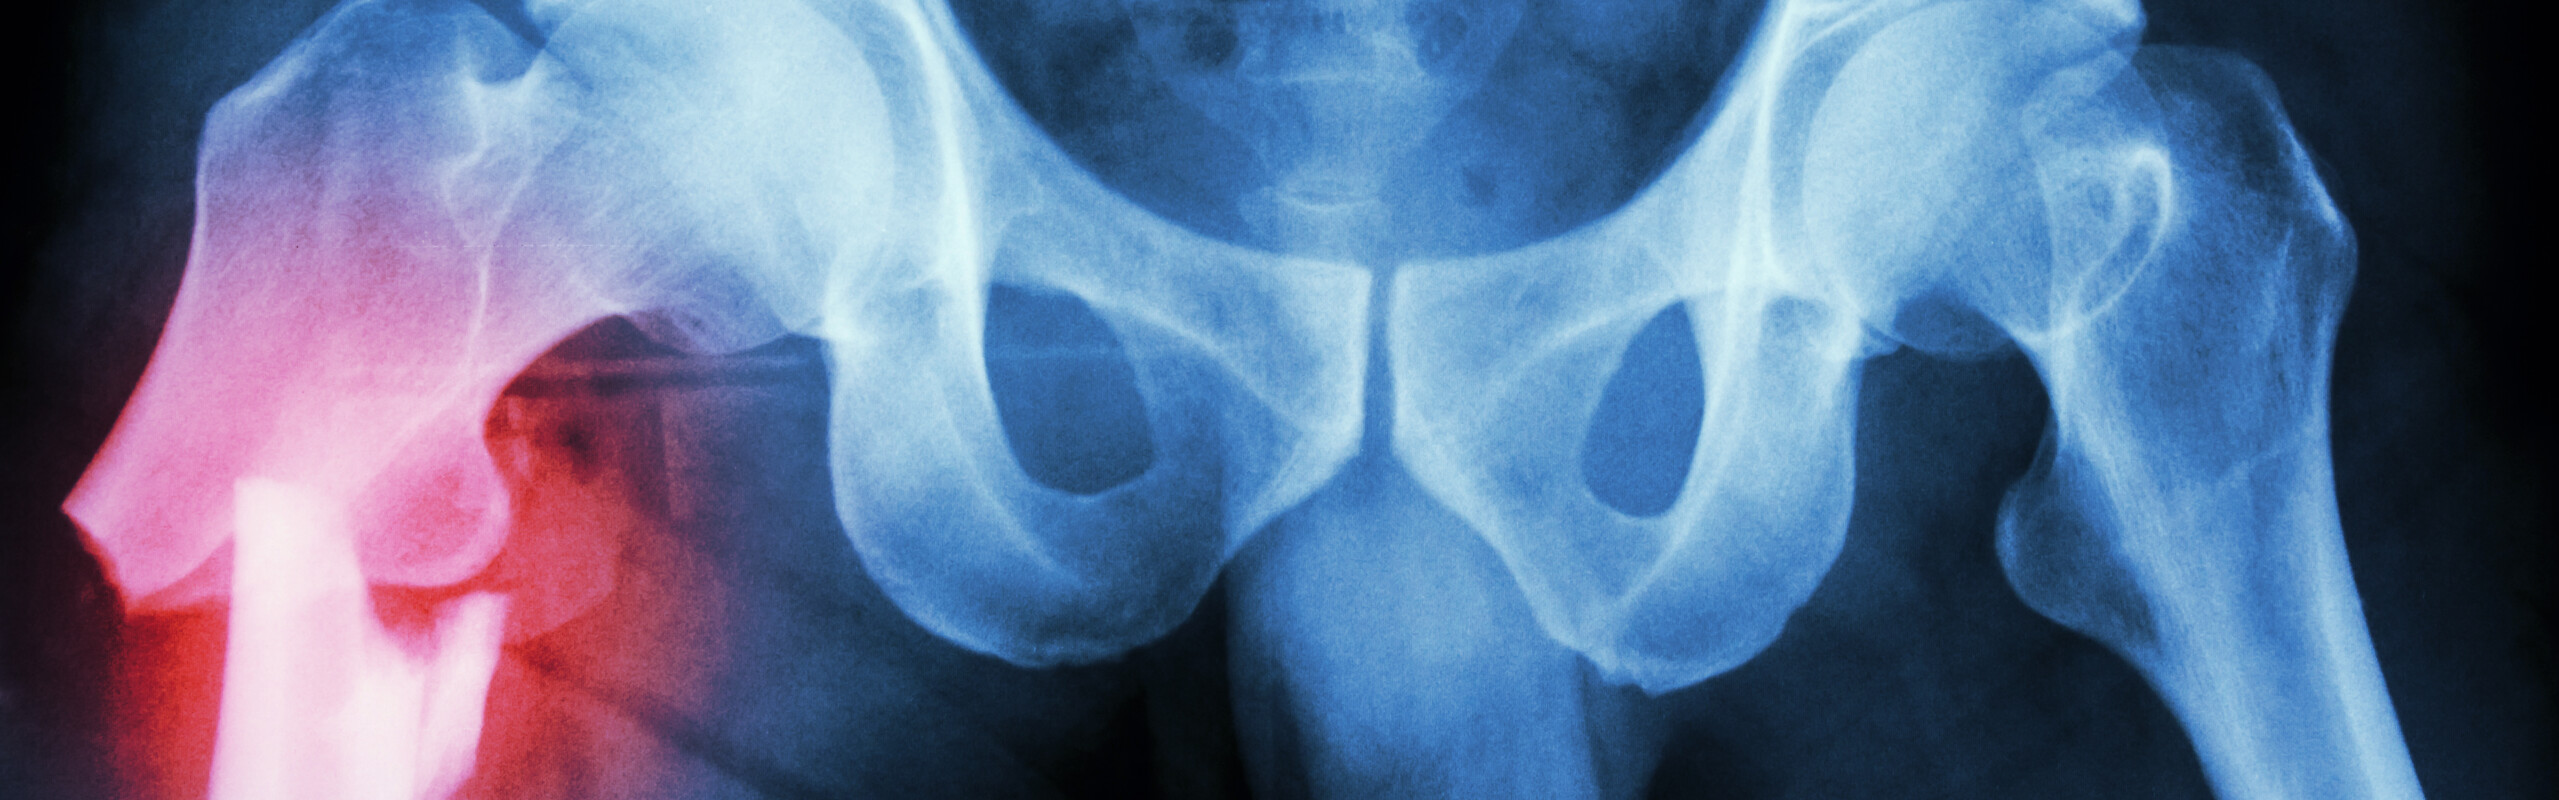

Bild: Mostphotos

Höftfraktur bland äldre personer - smärta, fysisk funktion och upplevelser av rehabiliteringsprocessen, depressiva symtom och mortalitet

Doktorandprojekt Spelar operationsmetod någon roll vad gäller smärta och funktion efter en icke felställd höftfraktur? Doktorandprojektet kommer jämföra smärta och funktion hos äldre personer beroende på operationsteknik, samt att beskriva patienternas upplevelse av rehabiliteringsprocessen över tid. Vi kommer undersöka sambandet mellan höftfraktur och depressiva symtom samt riskfaktorer för ökad 36 månaders mortalitet bland gamla människor, med särskilt fokus på delirium, demenssjukdomar och depressiva symtom.